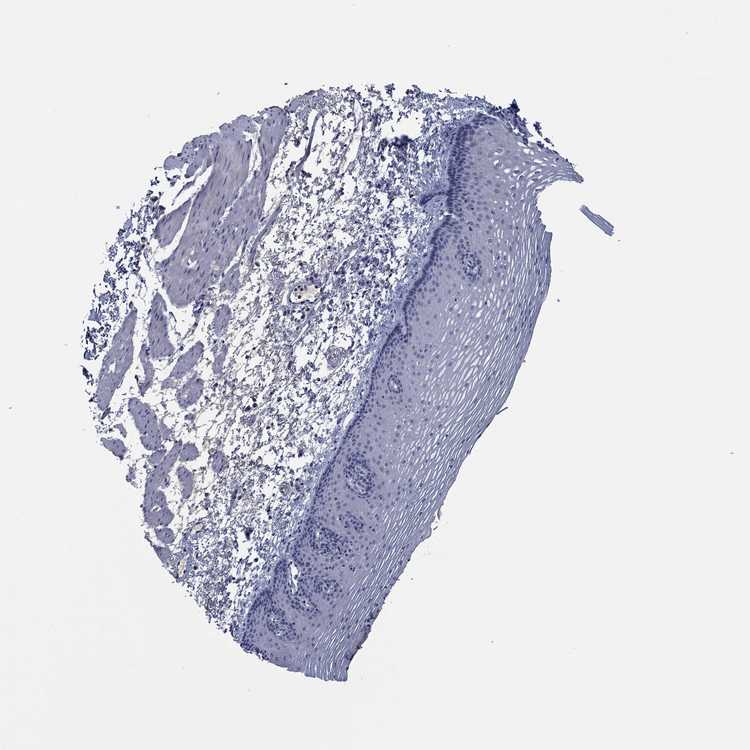

TISSUE PRIMARY DATA ESOPHAGUS Show tissue menu

Esophagus

ESOPHAGUS - Expression summary

ESOPHAGUS - Antibody stainingi

Antibody staining in the annotated cell types in the current human tissue is reported as not detected, low, medium, or high, based on conventional immunohistochemistry profiling in selected tissues. This score is based on the combination of the staining intensity and fraction of stained cells.

Each image is clickable and will lead to virtual microscopy that enables deeper exploration of all samples and also displays staining intensity scores, fraction scores and subcellular localization as well as patient and tissue information for each sample.

Antibody HPA012956Antibody HPA077702

Squamous epithelial cells MediumNot detected